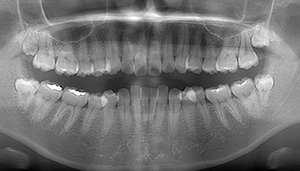

左上の親知らずが大きな虫歯になっていた症例

- 口腔内写真

- 抜歯前写真(レントゲン、CT等)

- 抜去歯の写真

| 年齢 | 30代・女性 |

|---|---|

| 主訴 | 虫歯の治療をしたい |

| 治療期間 | 1ヶ月 |

| 費用 | 約7,000円(保険治療内) |

| 治療方針 | 左上の親知らずをみてみると虫歯になっており、真っ黒になっていました。 そのため、虫歯治療ではなく、抜歯を行うことにしました。 |

| 抜歯内容 | 歯のクリーニング後、親知らずを抜いていきました。 |

| 特記事項 | 抜いた後は血圧が上がるようなこと(飲酒、運動、湯船に浸かる、マッサージ)などは行わないようにお願いします。 またドライソケット防止のために、抜いた箇所は触らないように、うがいも優しくするようにしてください。 歯ぐきに炎症がある場合は麻酔が効きづらくなりますので、炎症が治まってからの抜歯になります。 |